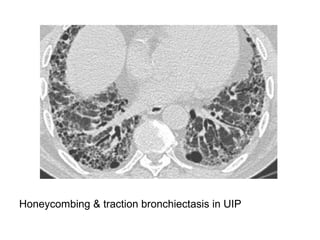

Honeycombing & traction bronchiectasis in UIP

Honeycombing comprises reticular densities caused by the thick walls of the cysts.

Whenever you see a chest film with long standing reticulation with a lower lobe and

peripheral preference

A, Unenhanced axial high-resolution CT through left mid (A) and lower (B) lung

show peripheral honeycombing, which is greatest in lower lobe,

accompanied by traction bronchiectasis and scattered peripheral reticular

opacities. Honeycombing is most prominent feature in this patient, typical for

idiopathic pulmonary fibrosis